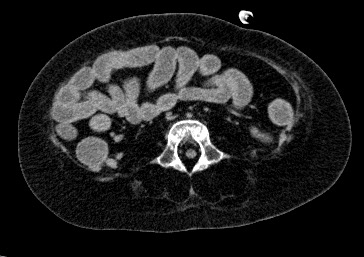

直腸にまで、液体が認められる

• 肝臓にはまだら脂肪肝と思われる不均一低吸収が認められる。膵、脾の形態、大きさ、内部の描出に異常指摘できず。

• 胃には、胃瘻があり、その先端は胃内にあり、胃内には、薬剤投与によると思われる高吸収の物質が胃底部に溜まっている。

• 両側腎も大きさ、位置に異常ない。両側腎内結石あり。

• 腸管の走行、外径、内部の濃度などに異常は指摘できない。直腸にまで、液体が認められる。下痢を起こしていたと考えられる。腸間膜の小さなリンパ節が多発で認められる。感染性腸炎の可能性はある。S状結腸に固体状の物質が認められる。由来が不明である。

• 全身の筋の脂肪変性または、筋委縮と脂肪浸潤が見られる。四肢などでは筋膜は保たれているようにも見える。骨も全体的にスレンダーである。